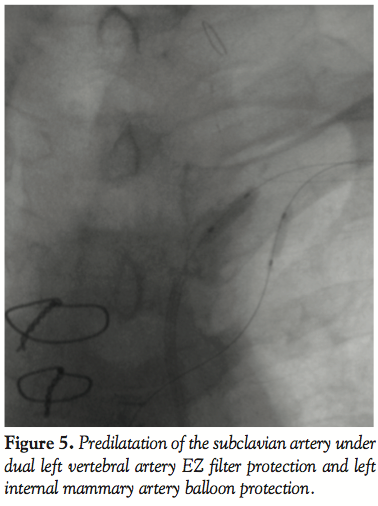

A 0.014˝ Choice PT graphix guidewire (Boston Scientific Corporation) was passed through the SC lesion via the transbrachial route with some difficulty. The guidewire was then advanced down into the iliac artery and pulled out of the femoral introducer using a GooseNeck snare (ev3, Inc., North Plymouth, Minnesota) (Figures 3 and 4). The wire was then introduced within a 5 Fr, 11 cm pediatric sheath (Cordis Corporation, Miami, Florida). A 5 Fr multipurpose guiding catheter (GC) was later advanced over the 0.014˝ wire and positioned just near the ostium of the left SC artery. The lesion was then predilated with a 2 x 20 mm and then a 3 x 20 mm Maverick balloon (Figure 5). Only then could the GC advance across the distal portion of the vessel to the lesion. At this moment, the 0.014˝ wire was removed and exchanged for a 0.035˝ wire (260 cm in length) through the GC. Then, the 5 Fr introducer femoral sheath was  exchanged for a 7 Fr, 61 cm SL2 sheath (St. Jude Medical, Daig Division, Minnetonka, Minnesota) positioned just near the ostium of the left subclavian and subsequently a 7 x 37 mm Express LD stent (Boston Scientific Corporation) was deployed in situ (Figure 6). Advancement of the GC across the lesion after predilation as well as all inflations within the SC artery were protected with prior LIMA 2.5 mm balloon inflation at 6 atm with subsequent deflation 5 seconds after deflating the subclavian balloon or stent. Post-dilatation of the stent was not performed. The LIMA balloon was withdrawn, then the Filterwire was retrieved with its  retrieval sheath (Boston Scientific Corporation) through the brachial sheath without any difficulty (Figure 7). The patient tolerated the procedure well and there were no complications. Some debris was retrieved in the Filterwire.